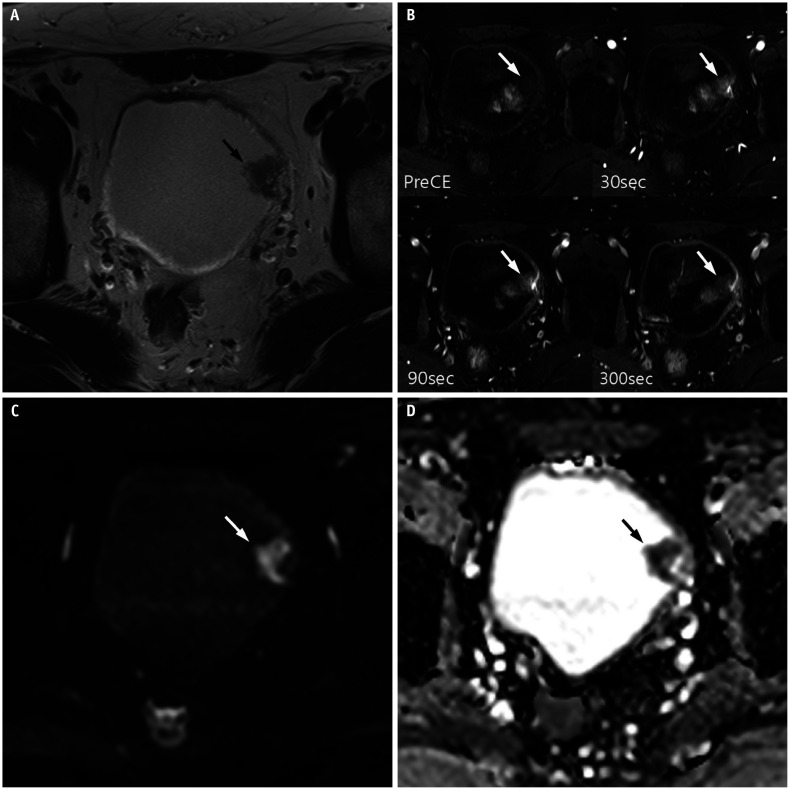

Results: PUC predominantly exhibited diffuse (6/13, 46.2%) or localized (5/13, 38.5%) bladder wall thickening. Diffuse thickening was often associated with a linitis plastica-like appearance. On high b-value diffusion-weighted imaging (DWI), eight and seven cases depending on readers (61.5% and 53.8%, respectively) showed mild hyperintensity or isointensity, with a mean ADC value of 1.1 × 10⁻³ mm²/s. Dynamic contrast-enhanced MRI revealed progressive and prolonged enhancement in 10 cases (76.9%). VI-RADS scores ≥ 4 were observed in 11 cases (84.6%). Histopathological analysis showed that tumors with progressive and prolonged enhancement contained myxoid stroma and some fibrous tissue. Interobserver agreement was excellent for most imaging features, except for good agreement on DWI signal intensity.

Conclusion: PUC demonstrates notable mpMRI features, including localized or diffuse wall thickening (often with a linitis plastica-like appearance), muscle-invasive and advanced disease, progressive and prolonged enhancement patterns, and mild hyperintensity or isointensity on high b-value DWI. These features, which are potentially linked to the myxoid stromal composition of the tumor, suggest that mpMRI may serve as a noninvasive diagnostic tool for this aggressive malignancy. However, further studies with larger cohorts are required to confirm these findings.